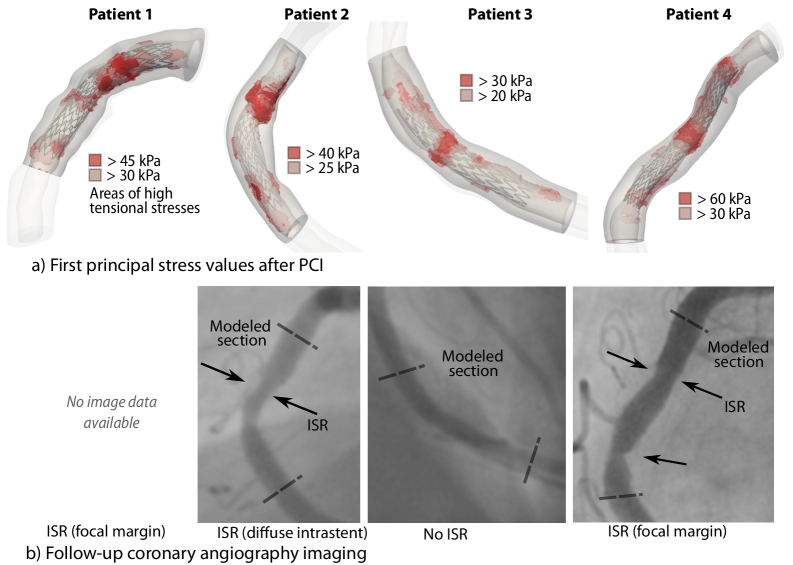

PCI with stent implantation is simulated as described in Section 2. We assess the mechanical state after the PCI, i.e., after the balloon withdrawal. Concisely, we review the first principal stresses, i.e., the stress values in the direction of the maximum tensile stress, as relevant mechanical value for vascular growth and remodeling Humphrey [2008]. Although tissue strains are also relevant for adaptation, we focus on stresses as they inherently account for both mechanical loading and material properties. D shows the stent placement, final stented artery, and a comparison of high-stress locations with the clinical follow-up angiography results in detail for each patient.

Refer to caption

Figure 6: Comparison of a) regions of high tensile stress after PCI simulation and b) angiography images at follow-up

At the maximum balloon expansion, we observe peak tensile stresses of 120 kPa. After the balloon withdrawal, the tensile stresses peak at around 30-60 kPa. Figure 6 summarizes the high-stress and ISR locations in the angiography for the four example lesions. The threshold values for the simulation results are determined based on the overall stress values: The first threshold (light red) shows the top 20% of the remaining stresses after PCI in the respective numerical example; the second threshold shows the top 5% (dark red). For Patient 1, no follow-up imaging was available, but only the clinical classification as focal margin ISR. From the remaining images, we observe that high-stress locations after the stent simulation tend to occur at ISR regions as seen in the angiography images. The simulation of Patient 3 shows no significant stress elevations in the stented area; the respective follow-up angiography also shows no signs of ISR. The simulated results comply well with the lumen gain, as seen in the angiography.

The areas of peak stress highly depend on the plaque morphology. In Patient 1, the lesion consists of mainly fibrotic and normal intima tissue with a small amount of scattered calcifications. The highest stresses are reached at the stent boundaries and in the most stenotic section. Patient 2 shows exceptionally high stresses in the proximal area, where a specific calcification pattern switches from a longitudinal shape to winding around the lumen. Additionally, elevated stress levels can be observed at the distal stent boundary. In the mainly fibrotic lesion of Patient 3, which did not show signs of ISR in the clinical follow-up, we simultaneously observed only mildly elevated stresses around the narrowest lumen area. Patient 4 shows high stresses at the stent boundaries and in the middle section, where the calcification pattern forms a circumferential pattern around the lumen.